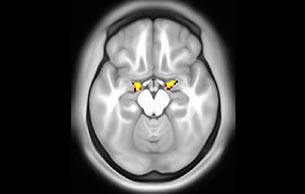

Resting state fMRI

Default mode network as discovered by resting state fMRI in one participant of the ALFA cohort [7]. rs-fMRI allows us to find networks of brain regions with highly correlated activity and sustaining distinct brain functions. The default mode network (in warm color scale) is active when the brain is focused on introspective thinking and has been shown to be altered in Alzheimer’s. Interestingly, brain areas of this network are known to show abnormal levels of one of the pathological hallmarks of Alzheimer’s (b-amyloid deposition) in preclinical stages. We want to better understand the alterations of these brain networks in preclinical stages of Alzheimer's and explore their potential use as biomarkers.

Imaging was performed using Ingenia 3T CX with a 32ch dS Head coil, TR 1.6 sec, TE 35 ms, voxel size 3.1 x 3.1 x 3.1 mm, 46 slices and Multiband SENSE factor 2. Image provided by Dr. Gispert